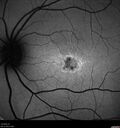

25 year old with Stargard and 2 ABCA4 mutations.vu 190 foisShe has worn glasses since she was a kid. Since she became an adult her vision started to deteriorate more rapidly. This seems to have been happening since she entered the accounting department for the last two years. Her vision is worse in the light especially when she is driving. She can see green lights in the night but not in the day. She sees better on a dark background than on a light background. Her mom is genetically visually impaired with Stargardts. Her father has RP. The mother was genetically tested in Boston about 23 years ago. That was when the gene was first being isolated. (The mother has seven brothers and sisters and four have stargardts and they are legally blind. Also one cousin has it.)

VA OD: Dcc20/160-1 PH20/80 Ncc20/200-2

VA OS: Dcc20/160-2 PH20/80-1 Ncc20/200-1

IOP: TP: OD:20 OS:21